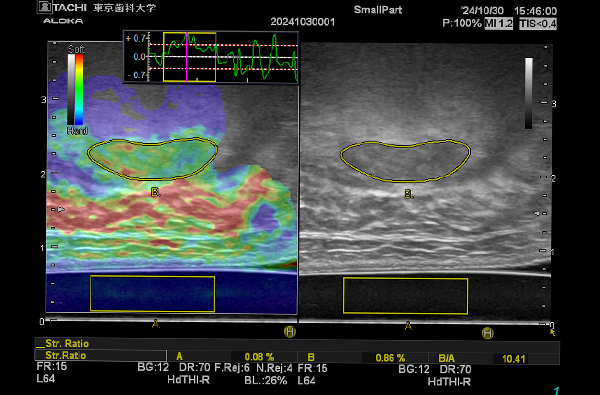

- 超音波エラストグラフィーによる機能評価

- 神経筋電気刺激による咀嚼筋増強効果と超音波診断による評価